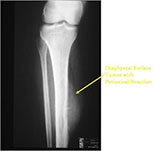

Plain X-Rays:

- Diaphyseal lesion on external surface of bone; medullary canal uninvolved

- Radiolucent mass extending into surrounding soft tissues

- Saucerized cortex with chondroblastic soft tissue mass that is usually primarily radiolucent on plain X-rays

- Periosteal reaction usually most evident feature on surface of bone (Hair on End or Sunburst appearance with spiculated pattern of calcification oriented perpendicular to the bone)

- Spiculated or sunburst periosteal reaction (due to periosteal elevation)